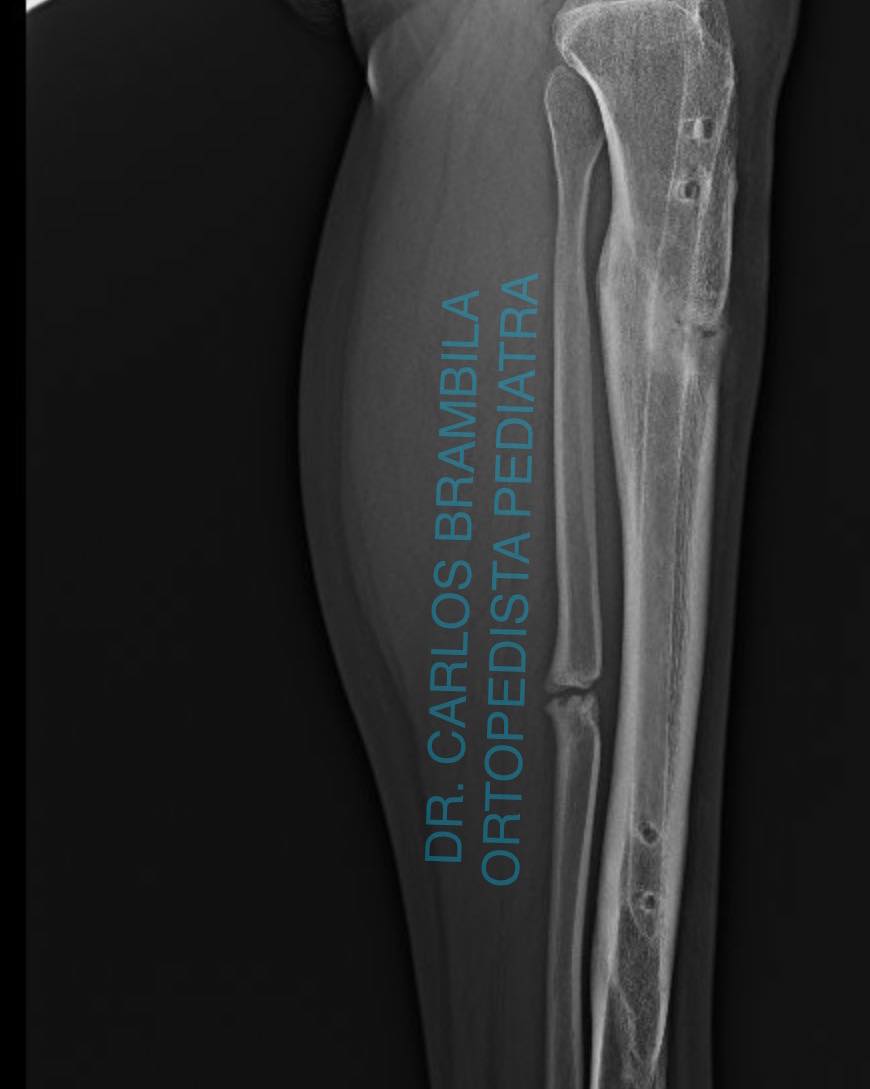

Me complace compartir con ustedes el caso de Karen, una joven de 17 años que acudió a mi consulta por un acortamiento en su extremidad inferior izquierda debido a una fractura de tibia. Después de una evaluación clínica y radiográfica, le realicé una cirugía de alargamiento óseo guiado con clavo centro medular y fijador externo Rekrea. El procedimiento fue un éxito, y Karen recuperó el balance de sus extremidades, eliminando el dolor en su cadera derecha. Ahora, Karen puede realizar todas sus actividades físicas sin problemas y se va feliz y satisfecha. Me siento orgulloso de haber podido ayudarla a recuperar su calidad de vida.